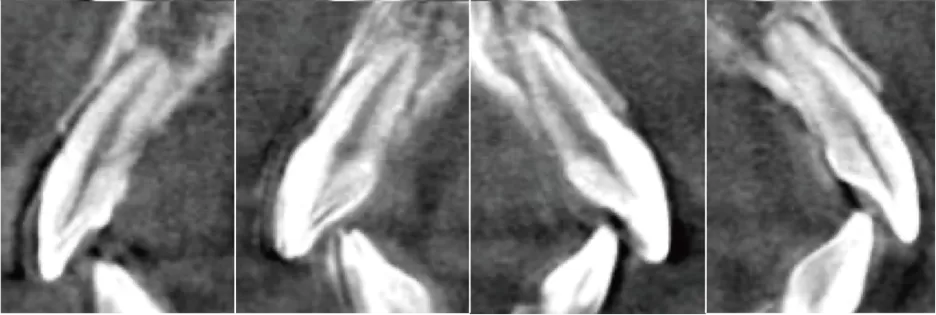

Centre de rotation intelligent S5

Rendre possible le mouvement précis des dents

Prévenir la fenestration des os et la déhiscence des os

Étape 0

Étape 7

Étape 28